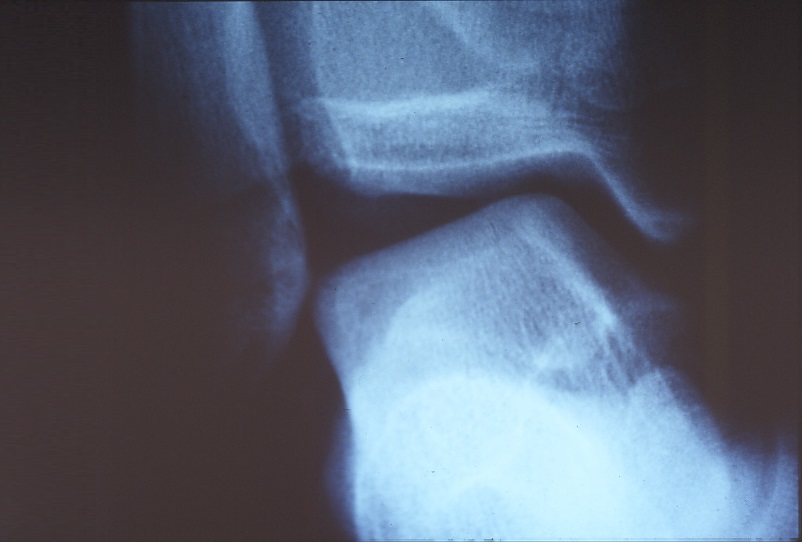

レントゲンチェックによる骨折の有無判定や、骨片の存在チェック、靱帯の緩みを調べるストレスレントゲン(写真3、4)、最近ではMRIや超音波検査で靭帯の有無、走行異常や肥厚像、出血などをチェックできます。

写真3 足関節は一見保たれている

写真4 同症例のストレスレントゲン写真は外側靱帯断裂のため足関節の傾きが明らかである。